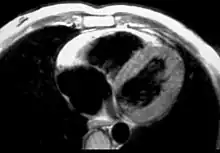

| Typical micro-histologic features of ARVC/D. Ongoing myocyte death (upper) with early fibrosis and adipocyte infiltration (lower). | |